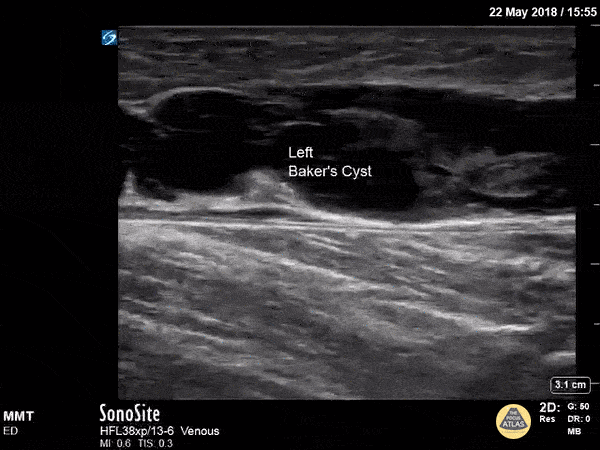

A longitudinal view of a ruptured Baker's cyst. When performing a DVT scan, always look out for incidental findings that may explain the patient's presentation! Dr. Michael Trauer